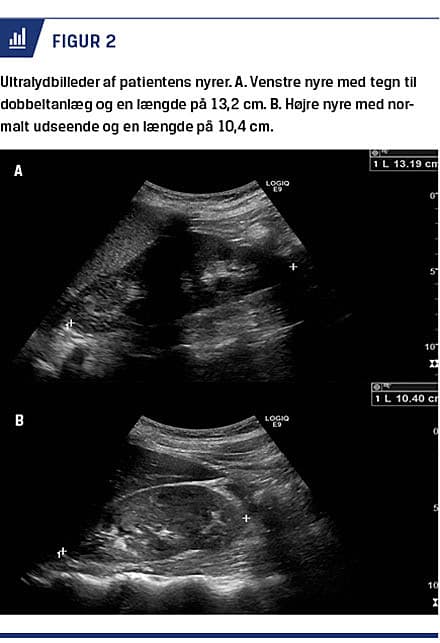

Kvinden var blevet spontant gravid og havde ikke tidligere haft aborter. Efter information om fundene ved operationen og betydningen heraf blev hun henvist til skanning af nyrer og urinveje. En ultralydskanning viste en forstørret venstre nyre på 13,2 cm i længden mod højre nyres længde på 10,4 cm. Der blev set tegn på todeling af venstre nyre, og der var mistanke om dobbeltanlæg (Figur 2).

Kvinden i sygehistorien havde et tæt på normalt graviditetsforløb trods sin sjældne og ukendte misdannelse. Hun blev spontant gravid uden problemer og gik i fødsel til termin. Hendes misdannelse i livmoderen har muligvis været medvirkende årsag til lav fødselsvægt, barn i underkropsstilling, mislykket vending og dermed forløsning ved kejsersnit. Hendes rygning er dog en kendt selvstændig risikofaktor for lav fødselsvægt [4]. En ultralydskanning viste tegn på dobbeltanlæg af venstre nyre på samme side som hendes rudimentære horn i uterus.